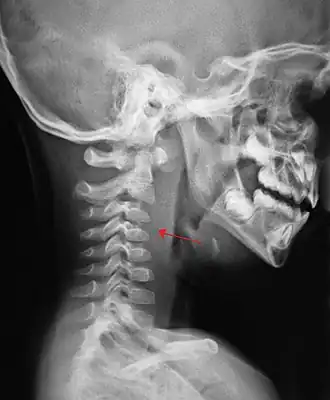

| Заглоточный воспалительный инфильтрат (рентгенограмма в боковой проекции) | |

Диагноз подтверждают при фарингоскопии, при которой обнаруживают флюктуирующую припухлость на задней стенке глотки. В первые дни заболевания шарообразное выпячивание задней стенки глотки расположено с одной стороны, а в дальнейшем — по средней линии. В сомнительных случаях производят диагностическую пункцию.